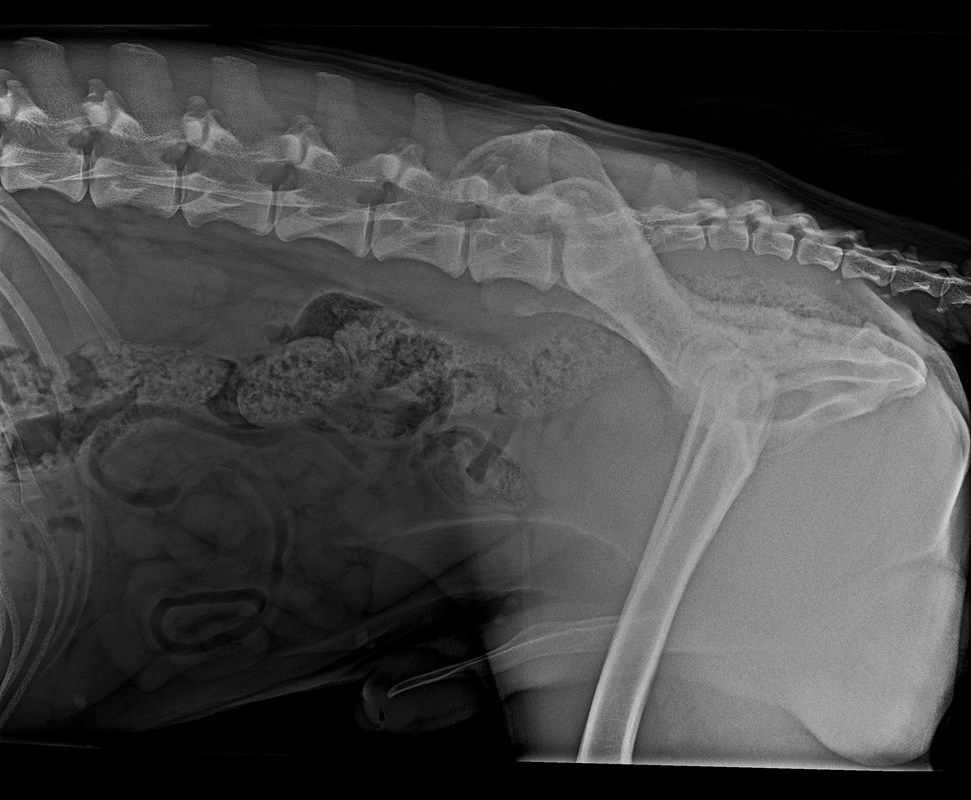

Wir warten jetzt mal die offizielle Auswertung ab. Bin auch gespannt, was nun bei OCD und Lendenübergangswirbel rauskommt. Und welcher LÜW-Typ.